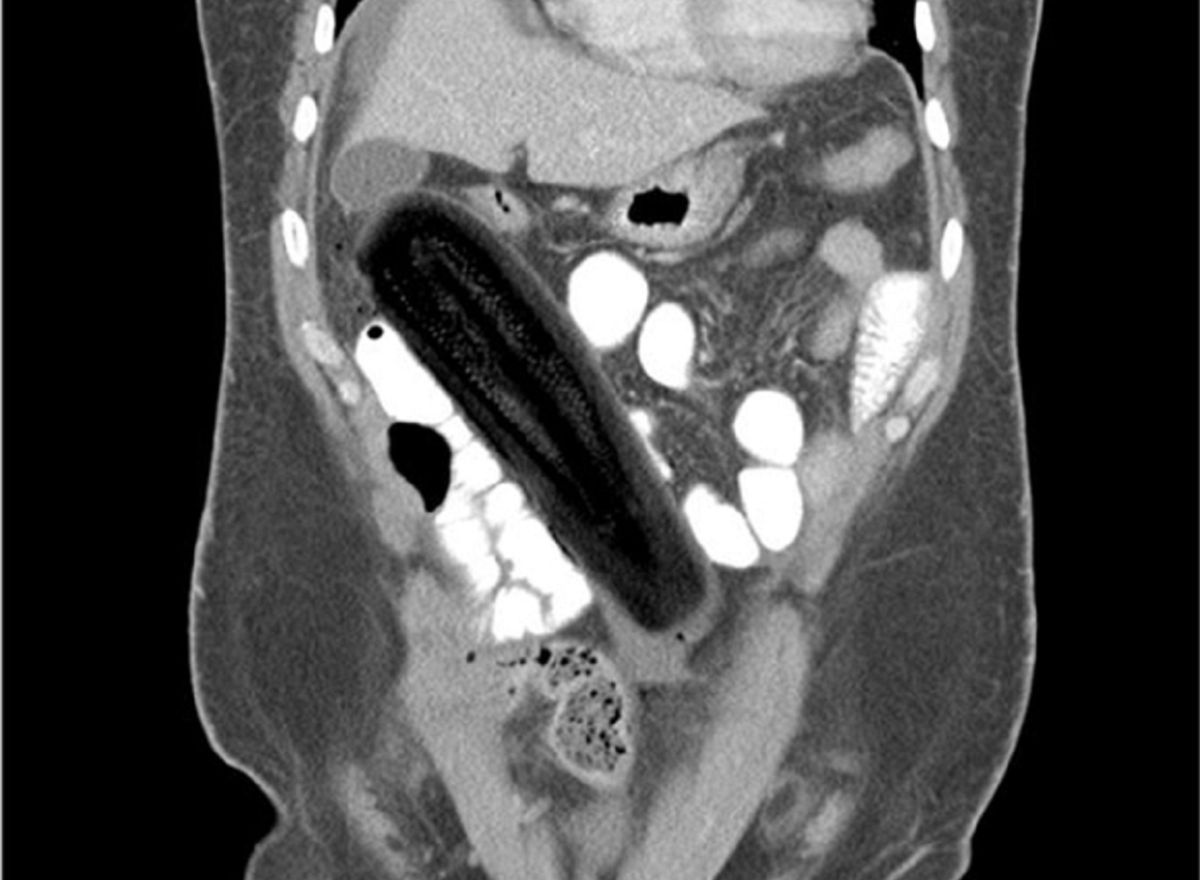

/ 8Cukinia

Obraz

© imgur.com

Ciekawe, co to był za przepis... Pacjentka tłumaczyła, że to miał być kulinarny eksperyment.